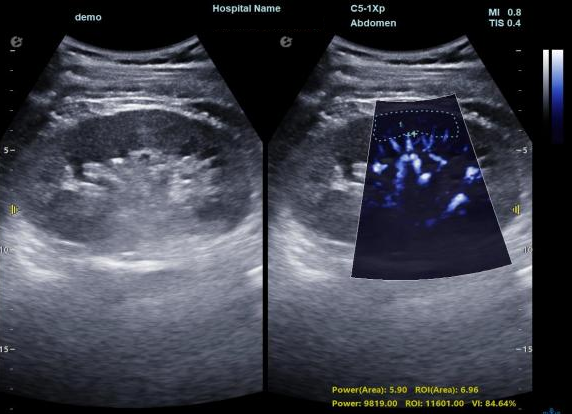

3) 通过血管指数(VI)定量评估局部血管密度,以定量化数据实时监测血流灌注情况,预判肾功能恢复情况;

肾脏的灌注评估,RI/VI量化数据

超微视血流显像评估肾移植术后灌注情况

这一项无创、无辐射操作简便且无需造影剂的黑科技,相当于用"高速摄像机"记录血液细胞的运动轨迹,让血管并发症"无处遁形。

从术前评估到术中到术后,再到终身监护,当20-50μm级的超微血流信号在屏幕上跳动,我们看到的不仅是技术的精进,更是生命的律动。iPlane Vascular正在重新定义肾移植监护的标准——让医生拥有了"显微视力",让每一个微小血管的异常都无所遁形,让每一次免疫排斥的萌芽都被及时扼制。